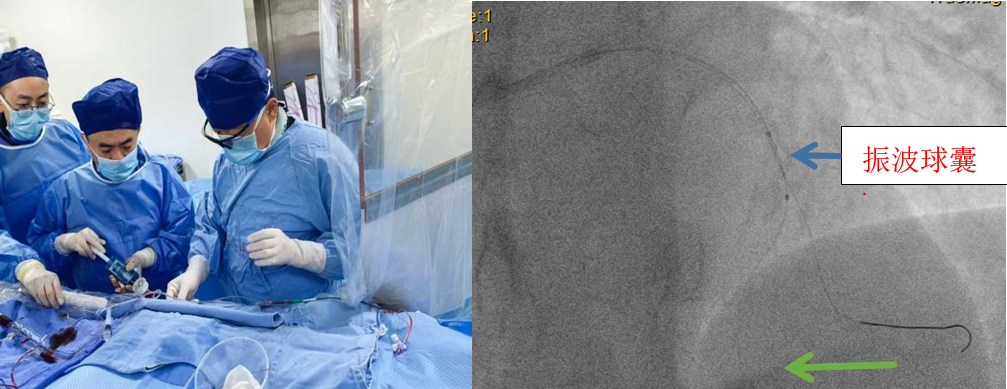

经充分沟通,戴闽主任团队决定采用全球创新的震波球囊技术。该技术通过球囊内低频冲击波精准碎裂钙化斑块,如同"血管内的微地震",在不损伤血管壁的前提下软化"钙化坚冰",为后续治疗创造条件。医院紧急调配设备,确保手术顺利开展。术后造影显示血管狭窄显著改善,患者恢复良好。目前,白先生已顺利出院。

戴闽主任介绍,冠状动脉钙化病变是介入治疗的"顽固堡垒",易引发血管损伤等并发症。震波球囊技术的应用,使以往"无法介入"或"高风险"的病例获得微创治疗机会,为患者带来「心」希望。此次手术的成功开展,体现了我院在复杂冠心病微创治疗的技术积累与创新能力,未来将惠及更多钙化病变患者。」